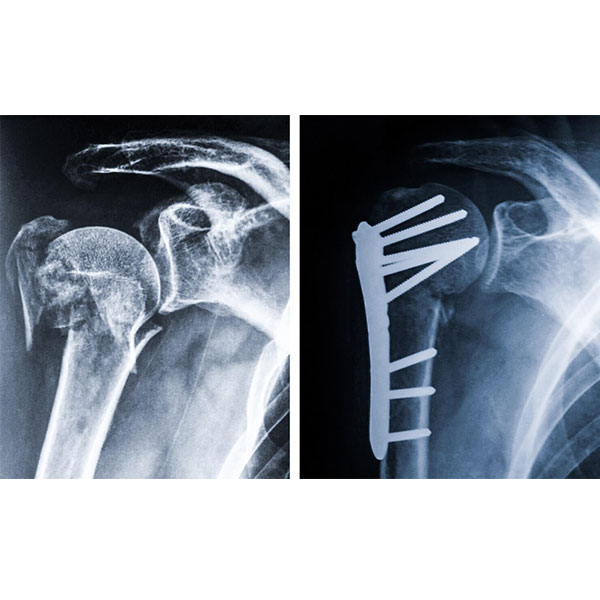

– Fraturas e sequelas de fraturas do úmero

– Artroplastias anatômicas e reversas do Ombro e Cotovelo